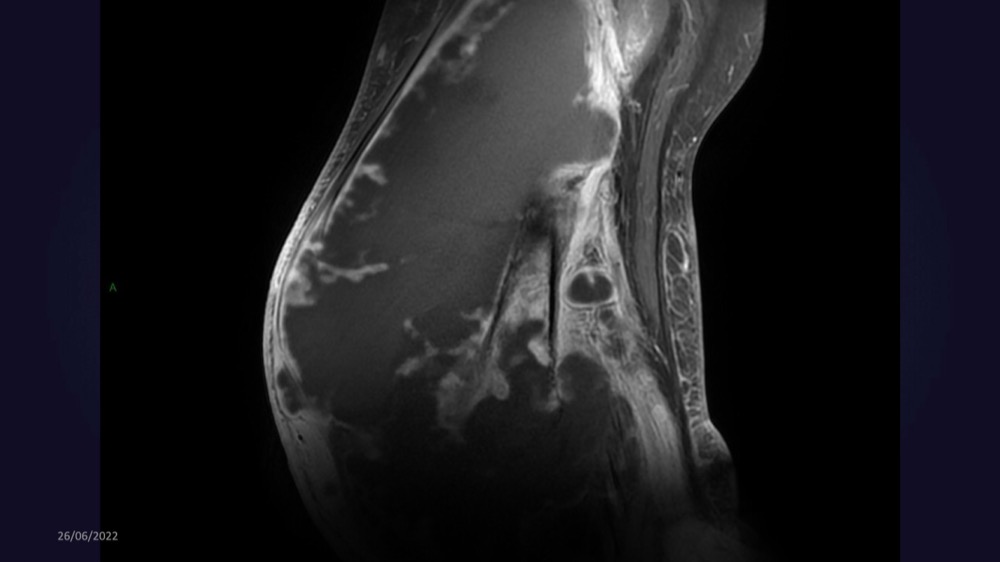

Reichert / Amar / Tordjman / Carlier 29/06/2022